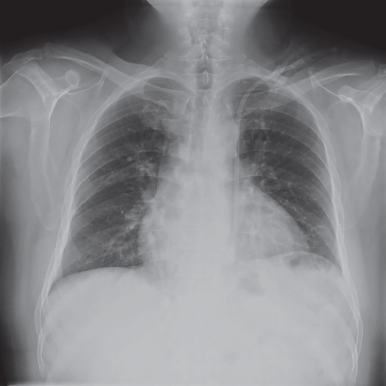

Figura 1 Radiografía simple de tórax, donde se observa catéter venoso central en vena cava superior izquierda

Se colocó un catéter Mahurkar sin complicaciones, pero en la radiografía de tórax figura 1 se observó una localización atípica. Por lo tanto, se solicitó una angiotomografía de tórax, la cual mostró imágenes relacionadas con la persistencia de la vena cava superior izquierda figuras 2 y 3, con el catéter venoso central en su interior, cuyo extremo se encontraba en el tercio distal vaso anómalo se originaba en la confluencia de la vena yugular interna izquierda y la vena subclavia izquierda, discurriendo inferiormente a la izquierda del arco aórtico y anterior al hilio pulmonar izquierdo, drenando finalmente en la aurícula derecha.